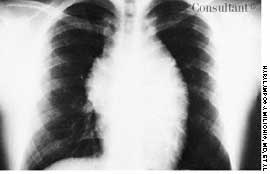

This rash, which covered a 68-year-old woman's body, was noted to have worsened during the past 2 months. A cephalosporin antibiotic had failed to clear the condition. The patient, a nursing home resident, suffered from emphysema, asthma, and heart disease. She had been receiving oxygen therapy and prednisone for 1 year.